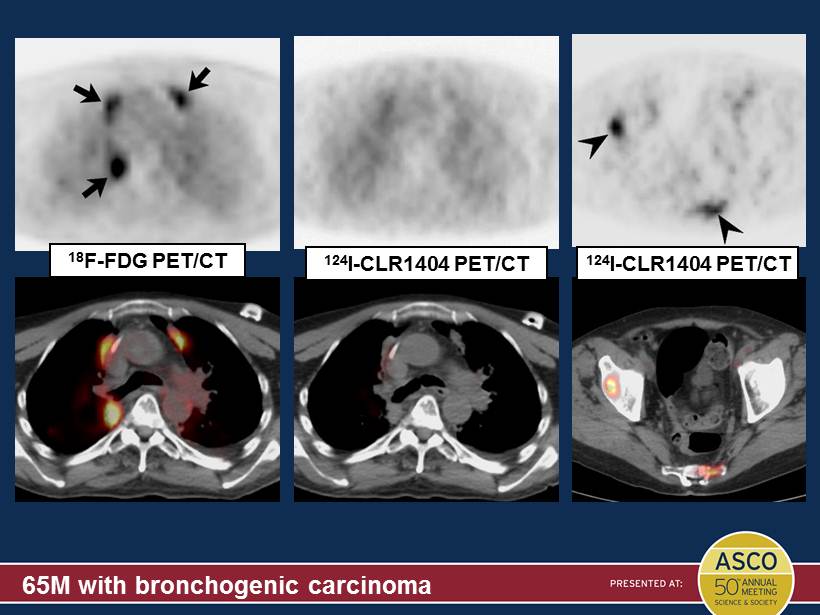

65M with bronchogenic carcinoma 124 I - CLR1404 PET/CT 18 F - FDG PET/CT 124 I - CLR1404 PET/CT